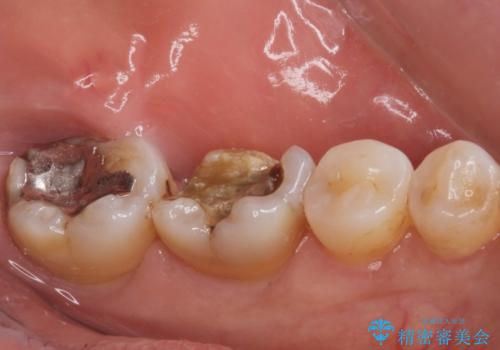

銀歯が取れた。

- 奥歯の銀の詰め物が取れたとの事で来院。

詰め物の下に虫歯ができて銀歯が取れてしまった事が予想されます。

白い詰め物でやり直しをしても歯質が薄くなり割れてしまうリスクがあるために、

割れるリスクの少ないジルコニアクラウンにて治療しました。